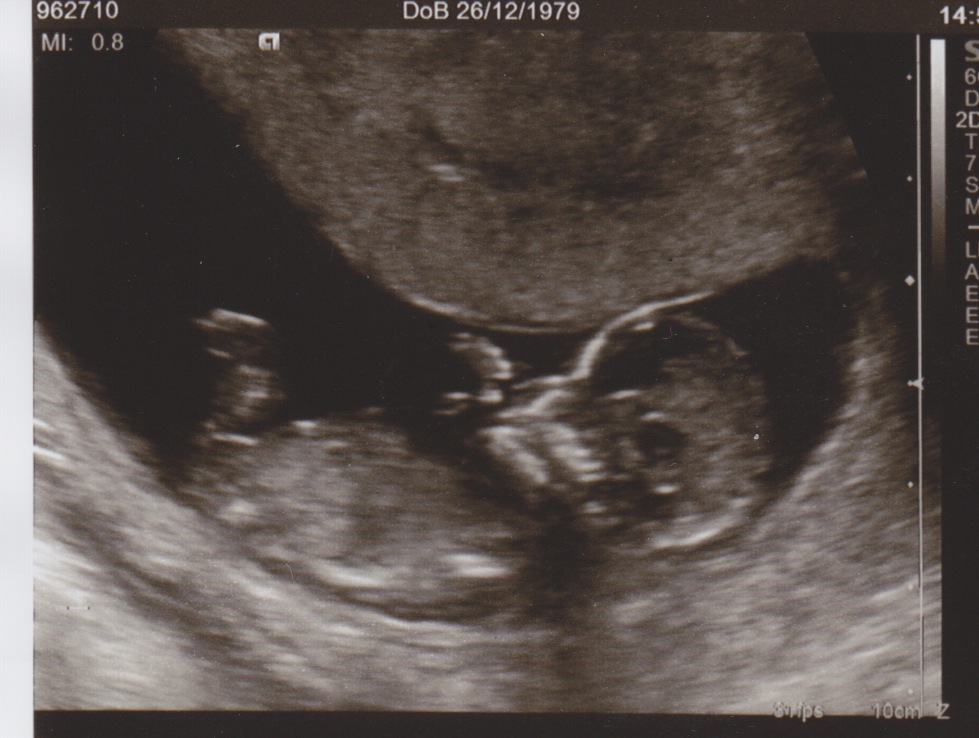

Here is my 7 week early scan, baby top left

Attachment 18832

and here is my dating scan at 12 weeks

Sorry no nub shots but predictions welcome

The nub is on there and I'll lean girl although there is a bump on top that's throwing me off so wouldn't be suprised either way!!